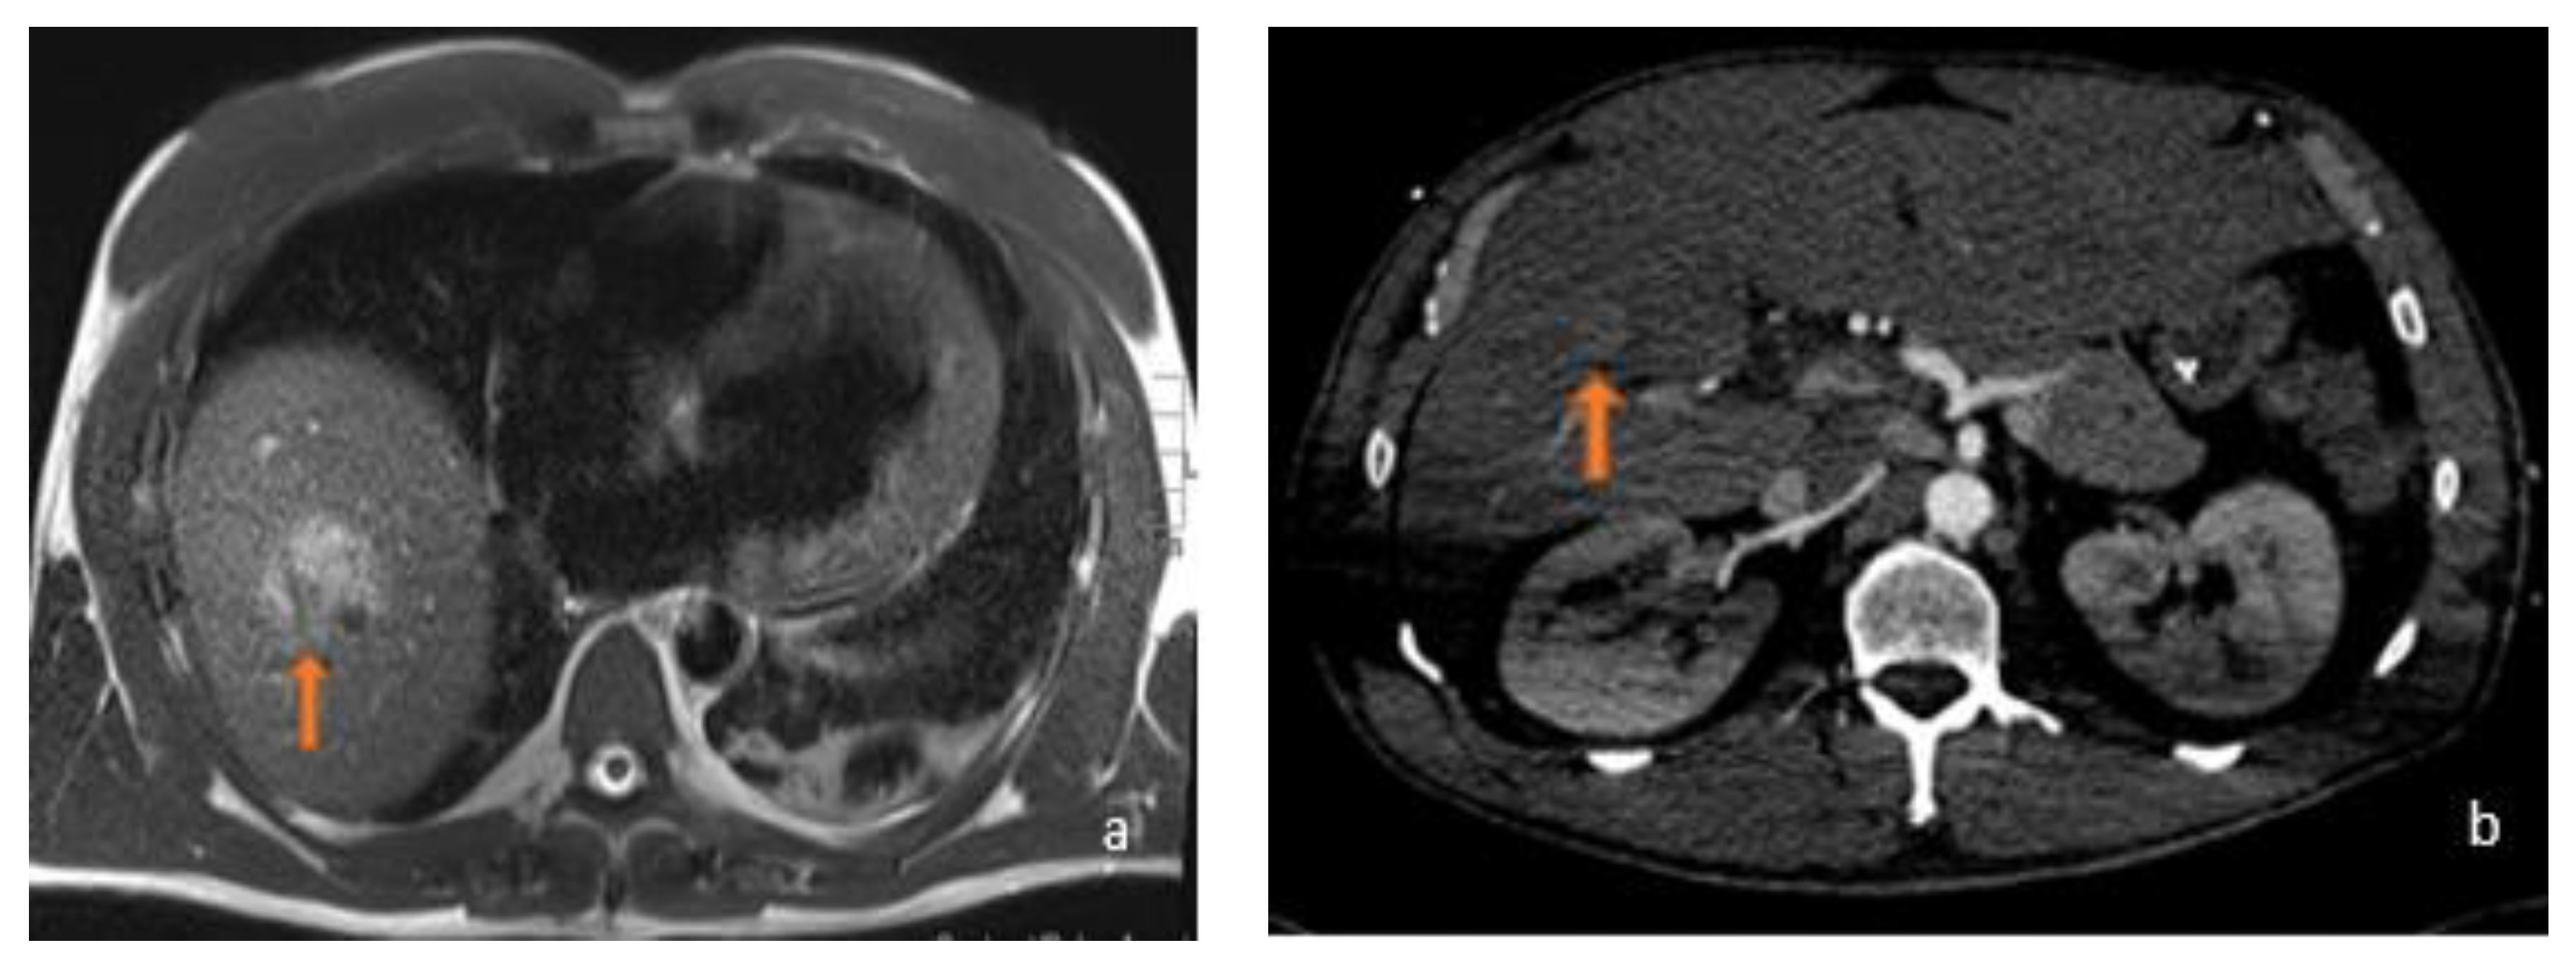

3.1. FLL Feature Characteristic

5.1. FLL Feature Characteristic

6. Benign MRI Features